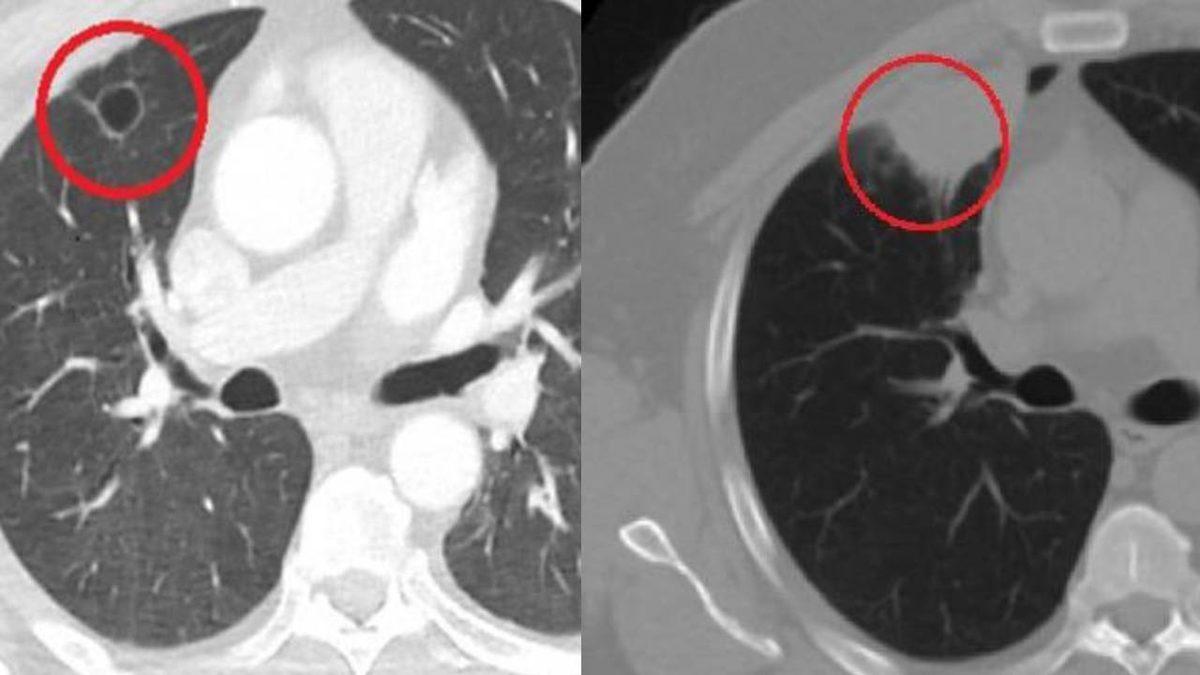

Sütçü İmam Üniversitesi Sağlık Uygulama ve Araştırma Hastanesi Göğüs Cerrahi Anabilim Dalı Öğretim Üyesi Dr. Fatoş Kozanlı da hasta için tomografi ve testler sonrası akciğer kanseri teşhisi koydu ve ameliyat gerektiğini söyledi. Gireceği operasyon öncesi PCR testi yapılan N.T.'nin testi pozitif çıktı ve COVID-19 tedavisi için ameliyat 14 gün ertelendi. Tedavi sürecinden sonra PCR testi negatif çıkan N.T. ameliyata alınmadan önce yeniden çekilen tomografide akciğerdeki tümörün tamamen yok olduğu tespit edildi.

Kozanlı hastanın durumunu "Hastamız, çalıştığı başka bir kentte göğsünden darbe alıyor ve ağrıları geçmeyince bir üniversite hastanesine başvuruyor. Burada hastaya bir akciğer grafisi çekiliyor. Sağ akciğerinde bir kitleye rastlanıyor. Daha sonra hastaya, bir akciğer tomografisi çekiliyor ve göğüs cerrahisi için önemli büyüklükte olan 4 santimetre çapında, akciğer kanserine benzer özellikte radyolojik bulgular olan bir kitle tespit ediliyor. Daha sonra hastaya yapılan ileri tetkiklerde akciğer kanseri teşhisi konuluyor. Hastaya bir cerrahi planlanıyor. Hasta Kahramanmaraşlı olduğu için kendi memleketine gelmeyi tercih ediyor. Bize başvurdu ve göğüs ağrısı şikayeti vardı. Öksürük, nefes darlığı, balgam çıkarma, ateş gibi şikayetleri yoktu. Hastayı biz de değerlendirdik ve ameliyat olmasına karar verdik. Çünkü akciğer kanserine çok benzer radyolojik bulguları vardı. Sağlık Bakanlığımızın kuralları gereği her hastayı ameliyat öncesi PCR testi yapılır. Biz de ameliyat gecesi hastadan PCR testi aldık ve testi pozitif geldi. Ameliyatımızı 14 gün erteledik ve hastamıza koronavirüs tedavisi uygulandı. Hasta 14'üncü gün tekrar bize başvurdu ve yapılan PCR testi negatif çıktı. Yeni bir tomografi çektik ve tümörün tamamen ortadan kalktığını gördük. Şimdi sonuç bilgilerinden başlangıca gittiğimizde, bu bir akciğer kanseri olsaydı, ortadan kalkması mümkün değildi. Başka bir patolojiye bağlı durum olsaydı, yine verdiğimiz tedaviyle ortadan kalkmasını çok beklemeyiz. Antiviral tedavisi verdik ve hastanın radyolojik bulguları neredeyse tamamen normale döndü. Hastaya bunu izah ettik, 'Dünya literatüründe hiç görülmeyen bir radyolojik bulgu' diyerek. Bu gördüğümüz manzara artık hastanın akciğer grafisinde yok, akciğer kanseri değil'' sözleriyle açıklarken varılan sonucun şaşırtıcı olduğunu ifade ediyor.